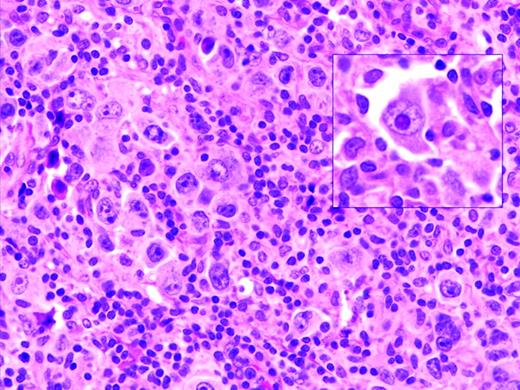

Oyama et al described EBV-positive B-cell lymphoproliferative disorders in elderly Japanese patients,38 and this lesion is now recognized as a provisional entity in the WHO classification as EBV-positive DLBCL of the elderly. It is defined as a histologically malignant polymorphic or monomorphic B-cell lymphoproliferation in patients who are generally over the age of 50 without any known immunodeficiency or prior lymphoma. The clinical behavior is aggressive, with frequent extranodal presentation and overall poor prognosis. Some cases show morphological overlap with classical Hodgkin lymphoma (cHL), also encountered in the elderly, but said to have a better prognosis.39 The lesion is thought be related to immunosenescence, the natural decay of the immune system as a consequence of aging.38 A recent large series of patients from the Western world showed overall similar clinical and pathological features, with a median age at presentation of 75 and an aggressive clinical course40 (Figure 1). However, despite the propensity to present at advanced age, identical lesions can be seen more rarely in younger patients, sometimes occurring close to the time of primary EBV infection.

EBV-positive DLBCL of the elderly. Large lymphoid cells, some with prominent inclusion-like nucleoli (inset) are seen in a background of lymphocytes and histiocytes. Large lymphoid cells are EBV positive with EBER in situ hybridization (not shown).